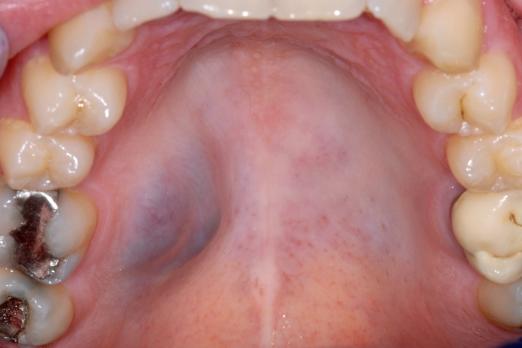

In de mond, en specifiek in het tandvlees, kunnen uiteenlopende afwijkingen voorkomen: van onschuldige veranderingen tot zeldzame, mogelijk levensbedreigende aandoeningen. Sommige afwijkingen komen ook op de huid voor of zijn het gevolg van medicatiegebruik. In deze e-learning leert u veelvoorkomende mondafwijkingen herkennen en onderscheiden op basis van hun klinische presentatie.

De cursus is thematisch opgebouwd rond categorieën als witte, wit-rode en rode afwijkingen, pigmentaties, zwellingen en ulceraties. Daarnaast wordt in een apart hoofdstuk stilgestaan bij tandvleesafwijkingen die niet plaque-gerelateerd zijn.

Met behulp van bondige teksten en duidelijke klinische afbeeldingen krijgt u inzicht in diagnostiek en classificatie. Ook leert u hoe u patiënten bij wie een mondafwijking wordt vastgesteld, op passende wijze informeert — zowel mondeling als schriftelijk.

Deze nascholing helpt u om afwijkingen tijdig te signaleren en professioneel te communiceren over de bevindingen, wat essentieel is voor goede patiëntenzorg.